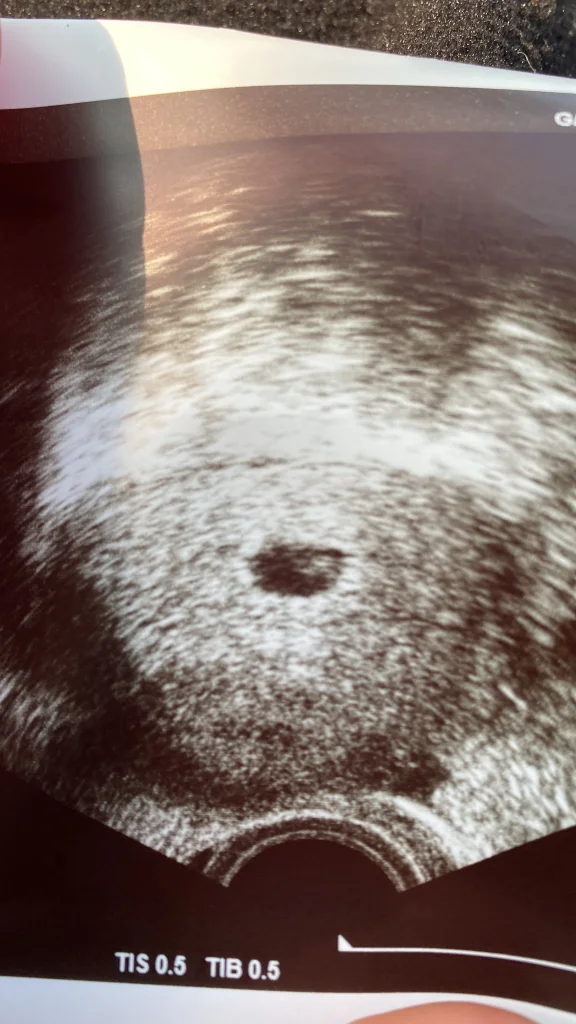

Amin 🤲🏻 vajinadan muayene oldum ben öyle göründü şükür içindeki bebek mi yolk sak mı bilemedm ama içi dolu ☺️

Maşallah canım kalp atışınıda duyarsın inşallah. Bende yarın gidicem kontrole. 5.haftaya giriyorum yarın artık görülür inşallah kese